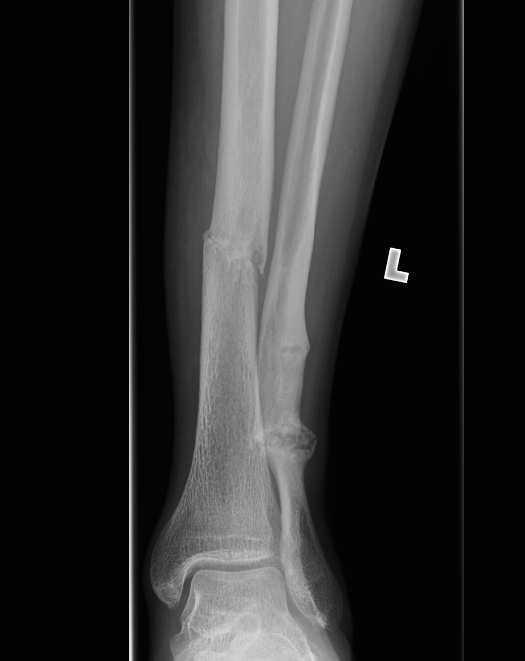

From eorif.com

Tibial Shaft Stress Fracture Images eORIF Stress Fracture Tibia Not Healing The vast majority of stress fractures will heal if treated correctly and promptly. Stress fractures take longer to heal and may require a brace, a walking boot, and crutches. Often you then see new bone growth where it has begun to heal. Learn how to prevent and treat them. Stress fractures are tiny cracks in bones often caused by overuse. Stress Fracture Tibia Not Healing.